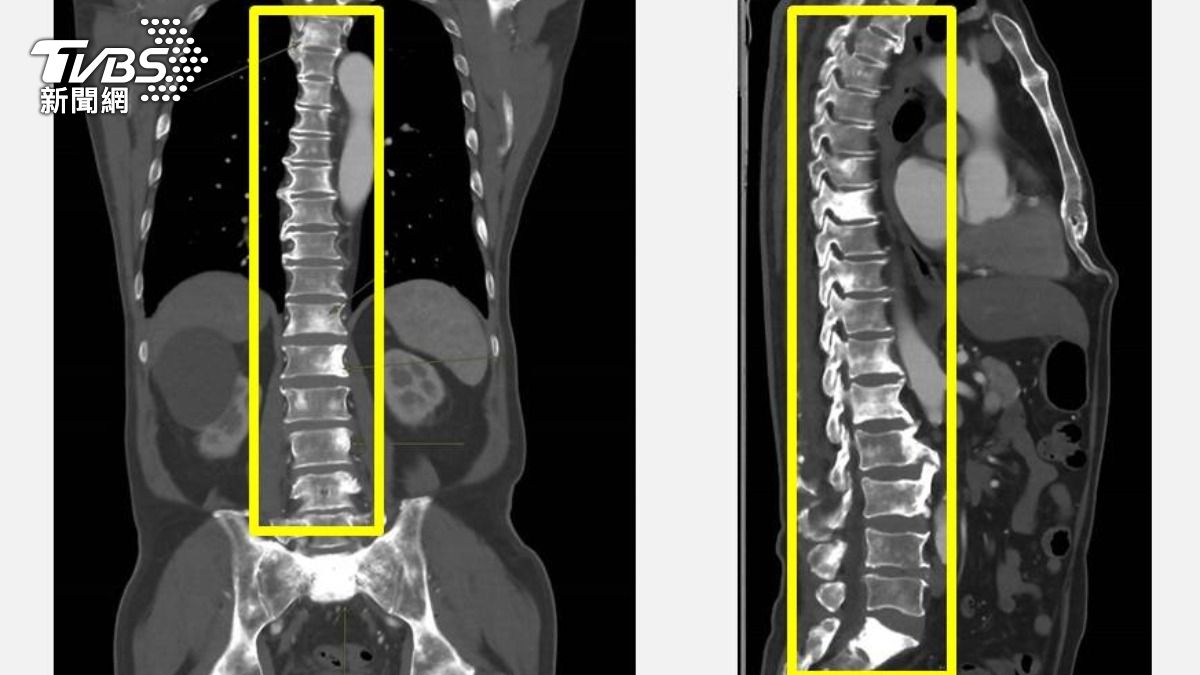

TVBS

高膽固醇是導致心血管疾病的隱形殺手,醫界向來將「降低膽固醇」視為預防心血管疾病的關鍵策略,不過,膽固醇越低越好嗎?一項國內醫界的研究指出,高齡族群若膽固醇過低或短期內劇烈下降,反而可能增加失智症發生與惡化風險。